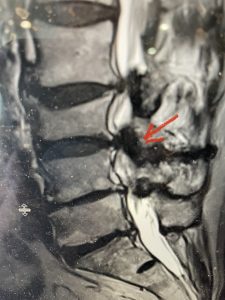

Epidural lipomatosis is a relatively rare condition where normally present fat in the epidural space is hypertrophied and can cause severe thecal sac compression. It is generally deposited more in the lateral and dorsal epidural space. This can be caused by long term steroid use and obesity, but also can be idiopathic. He had done well until more recently had developed low back pain with bilateral thigh pain and numbness. He had difficulty walking because of the pain. A new MRI (Fig 5) revealed that he had developed severe degeneration of the L1-2 segment above his prior decompression and fusion with a large extruded disc/osteophyte, right greater than left with severe thecal sac compression. He also had some residual T12-L3 residual epidural lipomatosis.

He had failed conservative treatment consisting of neurontin, physical therapy and epidural injections. He underwent revision laminectomy T12-L3 to decompress and explore prior fusion. He did have significant epidural fat encountered particularly at L1-2. The fat in epidural lipomatosis has a much more firm, globular texture. It takes a while to search within the fat, gently dissecting with a Penfield 4, to finally find the thecal sac! We encountered a large subligamentous extruded fragment lateral to the thecal sac on the right above the take off of the L2 nerve root. We removed any more residual fat at the L2-3 level and T12-L1 and decompressed the sac well. On exploration of the prior fusion it was fairly solid, but had some gaps at L2-3 fusion mass. Therefore we added a T12-L3 in situ fusion to augment those gaps and because we were at the thoracolumbar junction we extended fusion to T12. Post operatively he had relief of his leg pain.

(Figs 5a): Sagittal (a) and axial (b) T2-weighted lumbar MRI demonstrating status post lumbar decompression and insitu fusion L2-5 now well decompressed (blue dash) with development of new (red arrow) severe stenosis and with superimposed right L1-2 disc herniation (blue arrow)

(Figs 5b)